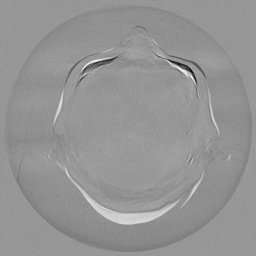

III-C Uncertainty analysis

Classical diffusion models reconstruct images by progressively denoising from an initial Gaussian noise image, a process that inherently introduces uncertainty due to random noise initialization. In contrast, I2SB directly learns a diffusion bridge between two sample distributions, effectively bypassing the need for random noise sampling and thereby reducing reconstruction variability.

To assess the uncertainty of our method, we performed multiple reconstructions using different random seeds. As shown in Fig. 3, the ground truth and representative sampled images are presented in Fig. 3(a) and (b–d), respectively. The mean reconstruction and pixel-wise standard deviation across runs are displayed in Fig. 3(e) and (f). Only minimal differences are observed between reconstructions, indicating that I2SB produces highly consistent results. These findings confirm that, compared with classical diffusion models, I2SB substantially reduces uncertainty across repeated reconstructions.